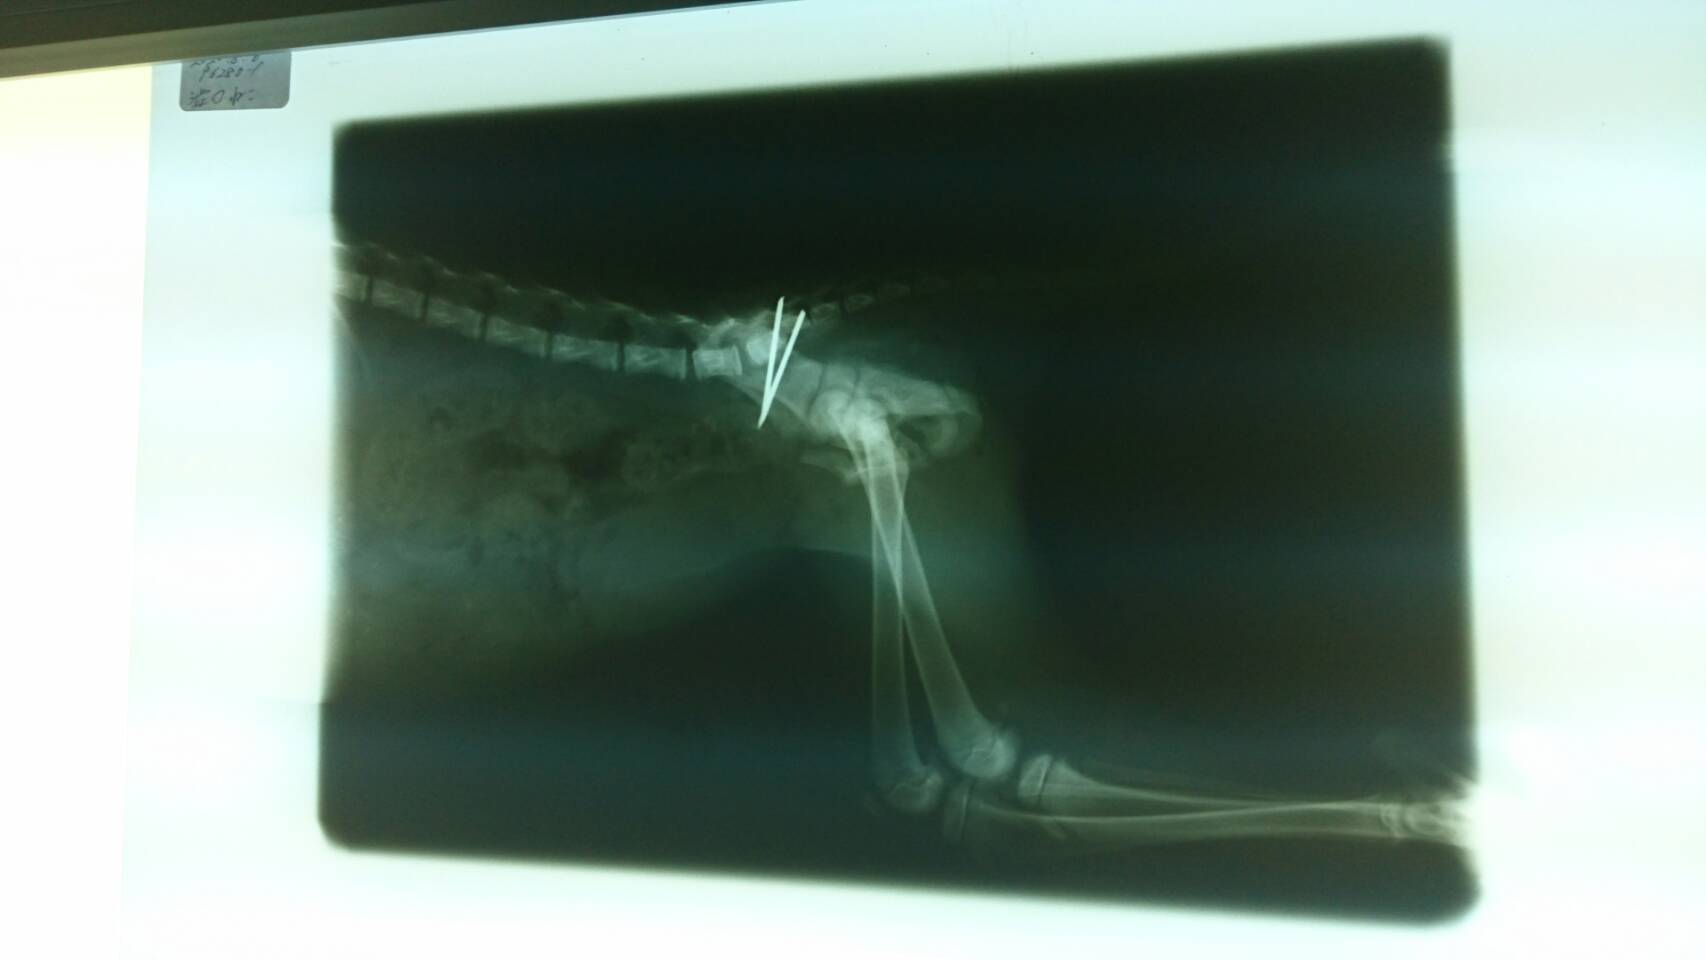

成猫だと骨盤をワイヤーで八の字に止める手術が多いそうですが、子猫の骨盤をワイヤーで固定すると骨の成長を妨げ将来障害が出る恐れがあるため、2本のピンで固定する手術をして頂きました。

ところが10日程立ち、レントゲンを撮って頂いたところ1本のピンが取れていました。

子猫の骨はまだ未完成で弱いため強く固定は出来ないそうです。